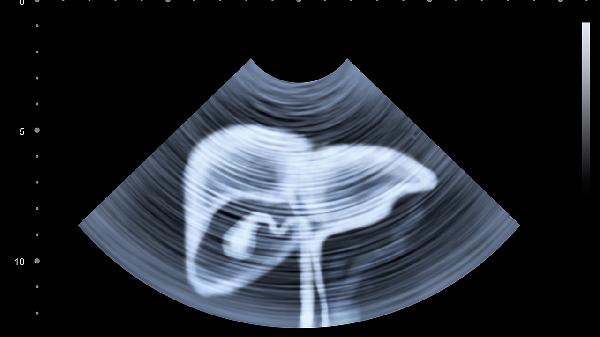

术后首次复查需进行腹部超声和血常规检查,确认无内出血或炎症指标异常。医生会根据手术范围、病理结果及营养状态开具个性化运动处方,通常从术后4周开始低强度有氧运动。